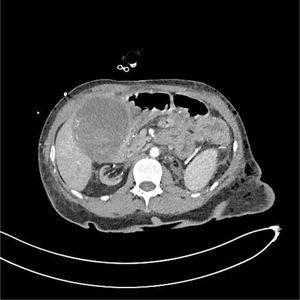

The patient is a 47-year-old female with a history of IgA nephropathy requiring a kidney transplant on 2 occasions and a right hemicolectomy due to intestinal perforation. In the immediate postoperative period after left nephrectomy due to a renal tumor, the patient presented hypovolemic shock secondary to necro-hemorrhagic cholecystitis, with active bleeding observed on CT (Figs. 1 and 2) performed due to suspected postoperative hemorrhage. Emergency cholecystectomy was performed, finding 500 cc of hemorrhagic content inside the gallbladder and active bleeding in the parietal peritoneum of the same, which was resolved after ligation of the cystic artery. The patient was discharged without complications.